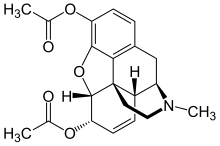

Propiedades físicas y químicas

Síntesis

Se obtiene mediante un proceso de acetilación de la morfina[53]

La materia prima para uso industrial o de laboratorio durante la síntesis de la heroína es la morfina. La acetilación con anhídrido acético o cloruro de acetilo se produce durante el calentamiento. No es necesario un exceso de cloruro de acetilo, ya que en este caso, el resultado, cloruro de hidrógeno, se une a la parte básica de nitrógeno núcleo morfinanovogo, y parcialmente retirado de la mezcla de gas que desplaza el equilibrio casi por completo hacia la formación de derivados diacetilados. El crudo de la acetilación se purifica por adición de carbón activo y filtrado para ser posteriormente recristalizado en etanol.

El rendimiento de la reacción es de hasta del 95,5%.[54]